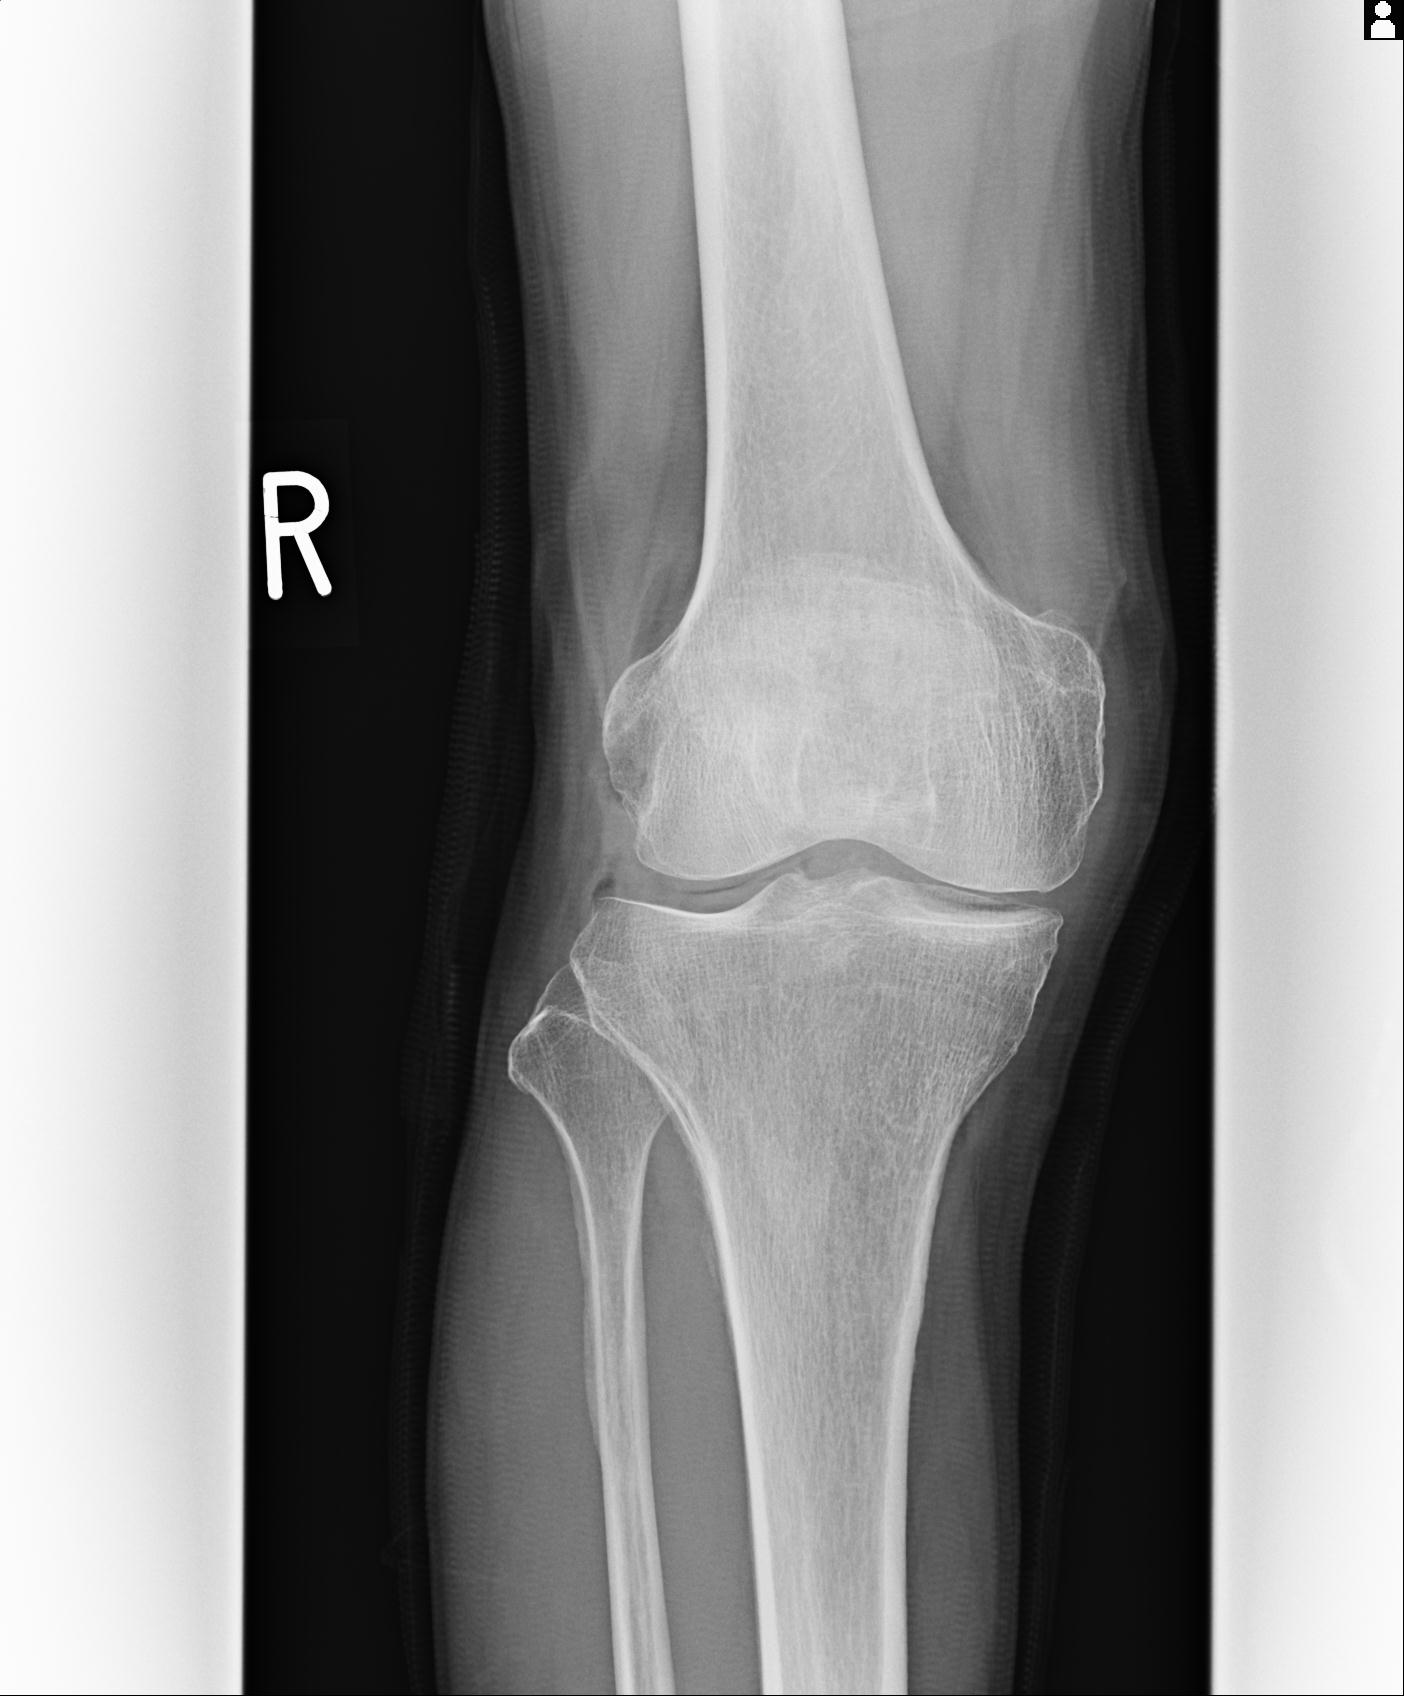

49554 3/13 膝 4R 3/16 4R 1/18 2R 78歳男性 膝蓋骨骨折

100612 11/25 1/20 右膝 2R 84歳女性 右TKA

91983 11/16 左膝 2R 11/18 2R 55歳男性 脛骨骨切り術